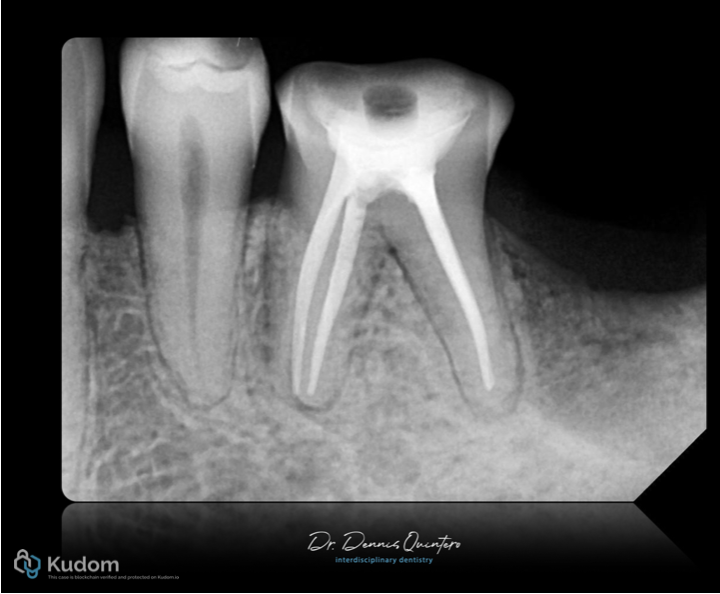

X-ray final result from endo to final conservative restoration